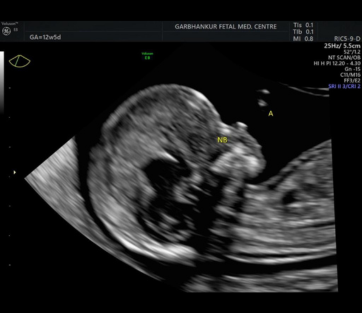

NT Scan

"NT scan," refers to a Nuchal Translucency (NT) scan.It is a prenatal screening test that assesses the risk of chromosomal abnormalities, particularly Down syndrome and other genetic conditions